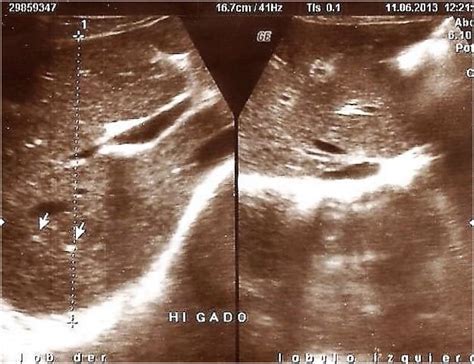

Ultrasound imaging, or ecography, is a crucial diagnostic tool in modern medicine, providing valuable insights into various medical conditions. One specific area of interest is the Parenquima Hepatico Izquierdo Ecografia, which refers to the ultrasound examination of the left hepatic parenchyma. This procedure is essential for diagnosing and monitoring liver diseases, assessing liver function, and guiding treatment plans. Understanding the significance of Parenquima Hepatico Izquierdo Ecografia and its applications can help healthcare professionals make informed decisions and improve patient outcomes.

Ultrasound imaging, or ecography, uses high-frequency sound waves to create images of internal body structures. This non-invasive technique is widely used in medical diagnostics due to its safety, affordability, and real-time imaging capabilities. In the context of Parenquima Hepatico Izquierdo Ecografia, ultrasound helps visualize the left hepatic parenchyma, identifying any structural or functional abnormalities.

Interpreting the results of a Parenquima Hepatico Izquierdo Ecografia involves analyzing the ultrasound images for any abnormalities in the left hepatic parenchyma. Common findings include:

• Hepatic Lesions: These can be benign or malignant and may appear as cysts, tumors, or nodules.

• Fatty Liver Disease: Characterized by the accumulation of fat in the liver, which can appear as a bright, echogenic pattern on ultrasound.

• Liver Cirrhosis: Advanced liver disease that can show signs of fibrosis, nodularity, and altered liver texture.

• Hepatic Vascular Abnormalities: Such as portal vein thrombosis or hepatic vein obstruction.